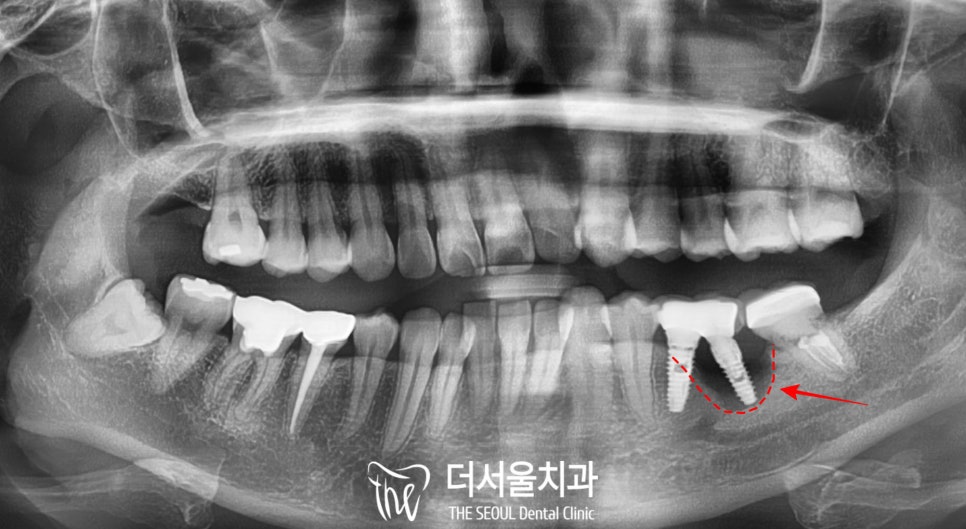

파노라마 엑스레이를 찍어서

불편감을 호소하시는 부위의

살펴보니,

두 개의 인공치근을 심고

그 상부의 보철을 브릿지로 연결해 둔

상태였는데

치근부에서

골소실 소견이 관찰되었습니다.